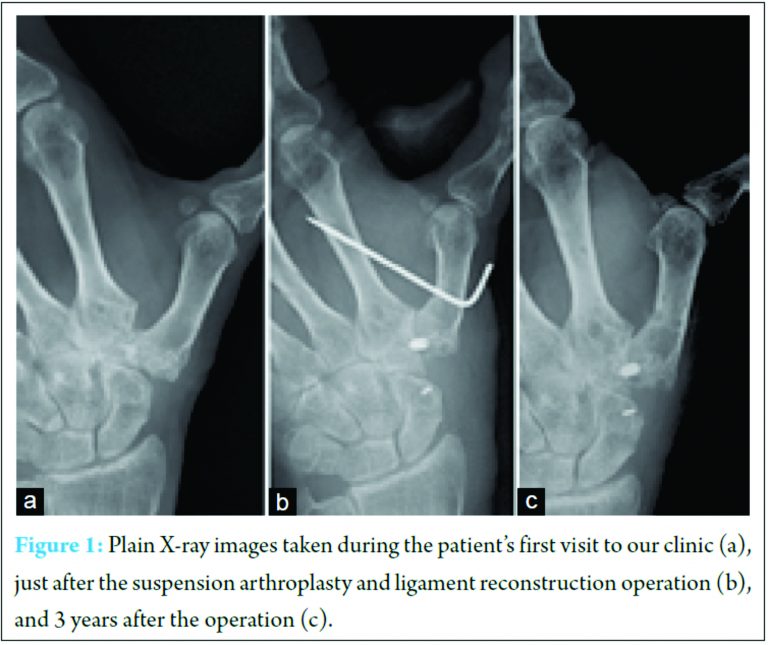

A 52-year-old female pianist developed arthritis of the left thumb CMC joint. After receiving conservative treatment for 6 months, she underwent LRTI arthroplasty using the FCR tendon after resection of the entire trapezius. 3 weeks of immobilization of the thumb in a spica cast was followed by range-of-motion exercises of the joint. She felt recurrence of pain in the base of the thumb 4 months after surgery, and a plain X-ray revealed that the first metacarpal had subsided and begun to touch the distal scaphoid. 8 months after the first LRTI procedure, she had the second LRTI surgery using a strip of the APL tendon. 6 months after that surgery, the thumb had moved proximally and was impinging on the scaphoid tubercle (Fig. 1a), and the patient again complained of joint pain. She was referred to our hospital 14 months after the first operation. She complained of tenderness in the base of the thumb and a deformity of the thumb demonstrating hyperextension of the metacarpophalangeal (MP) joint associated with flexion of the interphalangeal joint. Tinel’s sign was negative around the thumb. A xylocaine injection into the junction between the proximal first metacarpal and the scaphoid relieved the pain. She strongly desired to preserve motion of the CMC joint because she wanted to continue playing the piano. We performed the operation detailed below.

A 4-cm curved incision was created along the lateral margin of the first metacarpal and the proximal margin of the scaphoid tubercle. At the ulnar end of the skin incision, the half of the FCR tendon that had been used in the second operation was identified and exposed. The APL tendons, some of which that had been used in the first operation, were exposed at the radial end of the wound. The proximal base of the first metacarpal was in contact with the distal articular surface of the scaphoid. Removal of the soft tissue between the scaphoid and the first metacarpal base allowed the first metacarpal to be moved distally to a position that restored the normal joint junction between the first and second metacarpals. In that position, the proximal articular surface of the second metacarpal was seen through the trapezial void. Through multiple intermittent skin incisions over the ECRL, the ECRL tendon was exposed, and a 15 cm-long distal-based half strip of the ECRL tendon was harvested. A bone tunnel from the proximal dorsal cortex of the second metacarpal to the second CMC joint surface created during the previous operation was filled with scar tissue. A pilot pin was inserted through the tunnel, and the scar tissue was removed using a 3.2 mm drill bit (TJ screw system; Nakashima Medical Co. Ltd, Nagoya, Japan). Because of malposition of the bone tunnel made at the base of the first metacarpal in the previous operation, using the pilot pin and a 3.2 mm drill bit, we created a new bone tunnel from the first metacarpal just distal to the APL insertion to the most ulnar portion of the first CMC joint surface. The strip of ECRL tendon was passed through the bone tunnel into the second metacarpal base. The strip taken from the second CMC joint surface was inserted into the bone tunnel created in the first metacarpal base from the CMC joint surface and pulled out from its exit just distal to the APL insertion. The first metacarpal was distracted distally to level the joint lines between the first and second metacarpals. An interference screw (TJ screw; diameter, 3.5 mm; length, 7 mm) and a small piece of bone taken from the distal dorsal radius were inserted into the bone tunnel exit of the first metacarpal just distal to the APL insertion to fix the ECRL tendon strip. The distal ECRL tendon strip was subsequently passed three times around the FCR and APL in a figure-of-eight fashion to suspend the first metacarpal (Fig. 2). The end of the ECRL was passed dorsally and sutured to the ECRL remnant in an interlacing fashion (Fig. 3). A 1.5 mm K-wire was temporarily placed between the first and second metacarpals and removed 3 weeks after surgery (Fig. 1b).

A thumb spica cast was applied for 3 weeks after surgery, and a CMC joint soft splint was worn for a further 5 weeks. After the 8 weeks, the patient was encouraged to move the thumb and was allowed to play the piano. 3 years after the final operation, the thumb subsidence was measured as 3 mm on a plain X-ray compared with that obtained immediately after surgery, but the subsidence had not progressed when assessed 6 months after surgery (Fig. 1c). The patient demonstrated 30° hyperextension of the MP joint of the thumb, which was slightly better than that before surgery. The palmar and horizontal abduction were both 65°, and she could adduct the thumb to touch the palmar and radial side of the palm. Her grip strength improved from 12 kg preoperatively to 25 kg postoperatively. The tip and side pinch strengths had recovered from 1.2 kg and 2.8 kg preoperatively to 3.2 kg and 5.8 kg postoperatively, respectively. The patient felt no pain or paresthesia, but she perceived a slight solid feeling in the base of the thumb. She could play the piano without pain and was satisfied with the outcomes 3 years after surgery. The visual analog scale pain score at that time was 0.